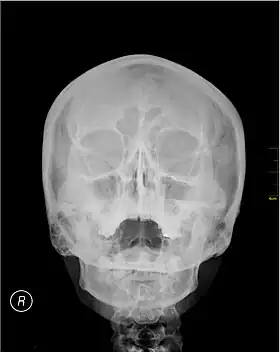

A Waters' view radiograph showing the paranasal sinuses

Waters' view (also known as the occipitomental view) is a radiographic view of the skull. It is commonly used to get a better view of the maxillary sinuses. An x-ray beam is angled at 45° to the orbitomeatal line. The rays pass from behind the head and are perpendicular to the radiographic plate. Another variation of the waters places the orbitomeatal line at a 37° angle to the image receptor. It is named after the American radiologist Charles Alexander Waters.